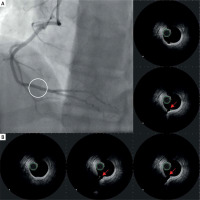

During the current hospitalization, coronary angiography with intracoronary OCT imaging was performed (Figure 1 A). Diffused atherosclerosis with a ruptured plaque in the right coronary artery (RCA) was identified (Figure 1 B). The patient was qualified for intensive conservative treatment. In addition, MRI confirmed the post-infarction scar of the entire thickness of the inferior wall with normal global systolic function. Pharmacological treatment, i.e., dual antiplatelet therapy (DAPT) for 12 months, β-blocker, and statin in the highest available dose, was included. After 3 months of follow-up, the patient remained free from angina and cardiovascular incidents.

Figure 1

A – Angiographic view of right coronary artery (RCA). Angiographically normal coronary artery. B – IVUS images of raptured plaque in the distal segment of RCA